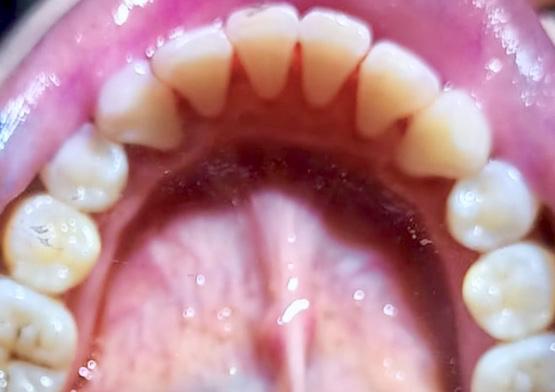

Hasil Scaling di Poli Gigi Alkindi

After